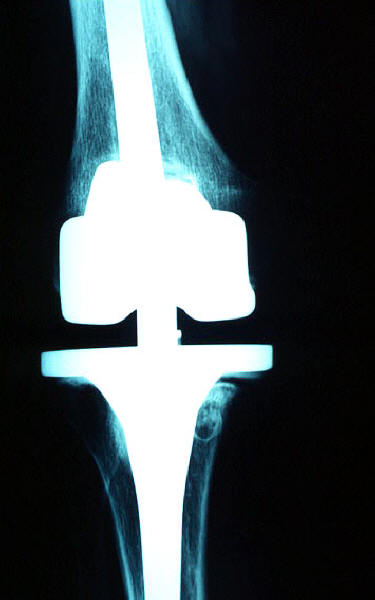

Prótesis completa de rodilla. Situación postquirúrgica.

Prótesis completa de rodilla. Situación postquirúrgica. Lateral.

Prótesis completa de rodilla.Lateral.

Prótesis completa de rodilla. Frontal.

Prótesis completa bilateral de rodillas.